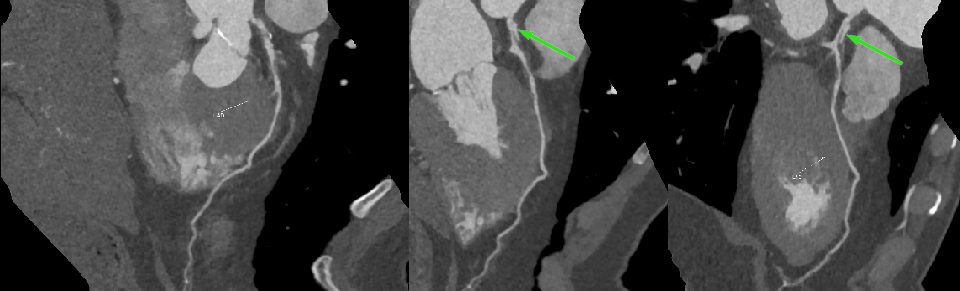

冠脉 CTA:

右冠状动脉近段双腔影,中段偏心性低密度,管腔中度狭窄。

1、考虑右冠状动脉近段夹层;右冠状动脉近中段偏心性低密度影,考虑壁间血肿,估计管腔重度狭窄

本例即为右冠状动脉近段 TYPE1 型,中段 TYPE2B 型;左冠状动脉前降支 TYPE1 型

冠状动脉 CT 血管成像(CCTA):随着 CT 空间和时间分辨率的提高,CCTA 逐渐成为 SCAD 的一种非常有用的无创性成像技术。CCTA 分型与有创冠状动脉造影分型相一致。CCTA 可能会出现的影像征象包括夹层内膜片影、壁内血肿、管腔锥形狭窄、突然管腔狭窄、管腔闭塞、血管周围脂肪堆积和血管相应心肌灌注减低。CCTA 有助于评估 SCAD 患者的其他血管病变,是随访监测的首选方法。